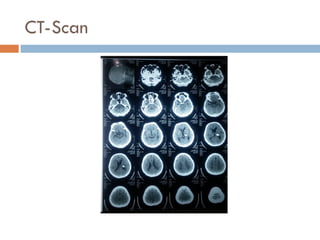

 Hasil CT Scan Kepala, potongan axial tanpa kontras:

 Tampak lesi hemoragik 12 x 13 x 13 mm parietalis kiri

 Mid line deviasi ringan kanan

 Sulci & ventrikel lebar

 Sela tursika; bentuk, ukuran baik

 Kalsifikasi plexus ; pineal

 Infratentorial baik

 Kesan : Stroke Hemoragik Parietalis sinistra